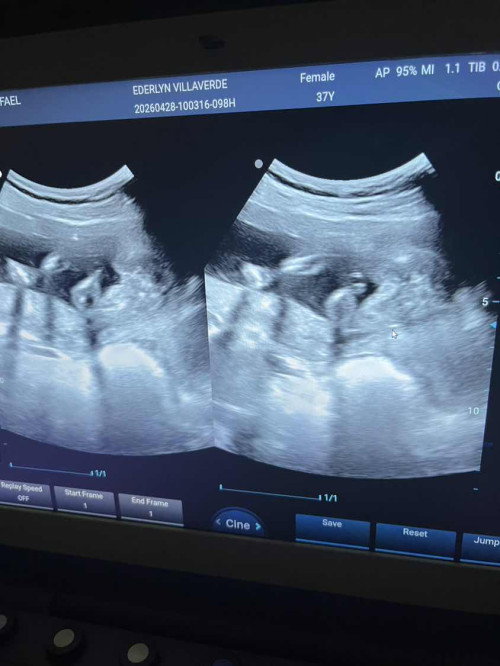

Nagpagender ako khapon 19wks na sabi babae pero nkadapa kasi c baby at diko din nkita yung genital pwede kayang mali ang sonologist my alam ba kyo na nagkamali na ang sono? Thanks panganay ko kc bby girl na sana itong bunso boy naman kasi CS ako hirap manganak high risk pa. Thanks po sa sasagot. #19_weeks1day